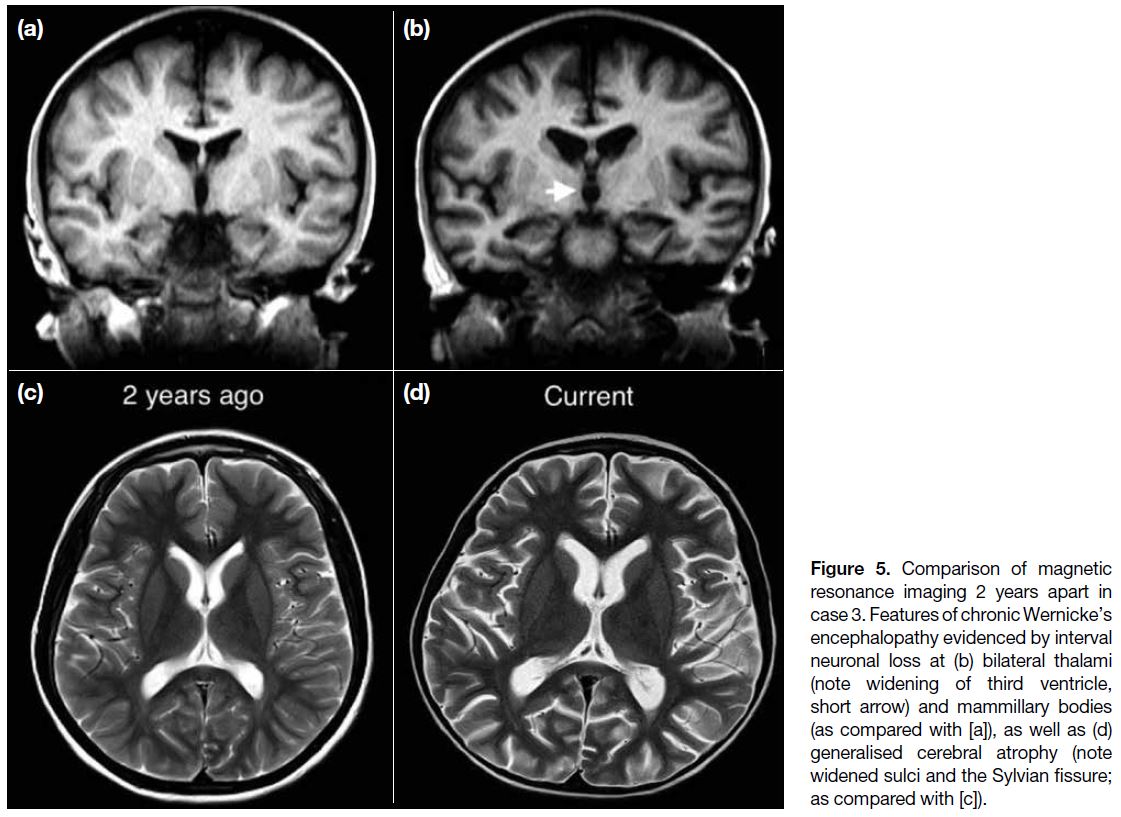

Case 3

A 12-year-old boy was on monoclonal antibody therapy

for recurrent atypical haemolytic uraemic syndrome. He

had experienced bouts of pancreatitis over the years and

was put on bowel rest and TPN episodically. He developed

lethargy, unsteady gait and vertical nystagmus 1 week

after the current episode of TPN. Compared with MRI

images 2 years previously, there was generalised cerebral

atrophy, with volume loss most significant at bilateral

thalami (evidenced by widening of the third ventricle),

mammillary bodies, colliculi, and hippocampi (Figure 5). Features and interval changes were highly suggestive

of chronic WE. This suspicion was substantiated by

interviews with the carer who reported past episodes of

abnormal behaviour in the form of disinhibition and limb

twitching. He was prescribed thiamine (1000 mg daily)

and resumed enteral feeding. His gait disturbance and eye

signs soon subsided but he remained underperforming in

academic and social aspects.

Figure 5. Comparison of magnetic resonance imaging 2 years apart in case 3. Features of chronic Wernicke’s encephalopathy evidenced by interval neuronal loss at (b) bilateral thalami (note widening of third ventricle, short arrow) and mammillary bodies (as compared with [a]), as well as (d) generalised cerebral atrophy (note widened sulci and the Sylvian fissure; as compared with [c]).

In chronic WE, the brain can show necrosis, gliosis, and

neuronal loss.[11] As illustrated in case 3 (Figure 5), these

changes can be gradual and subtle. Thus, it is salient that

a comparison has to be made with prior imaging studies